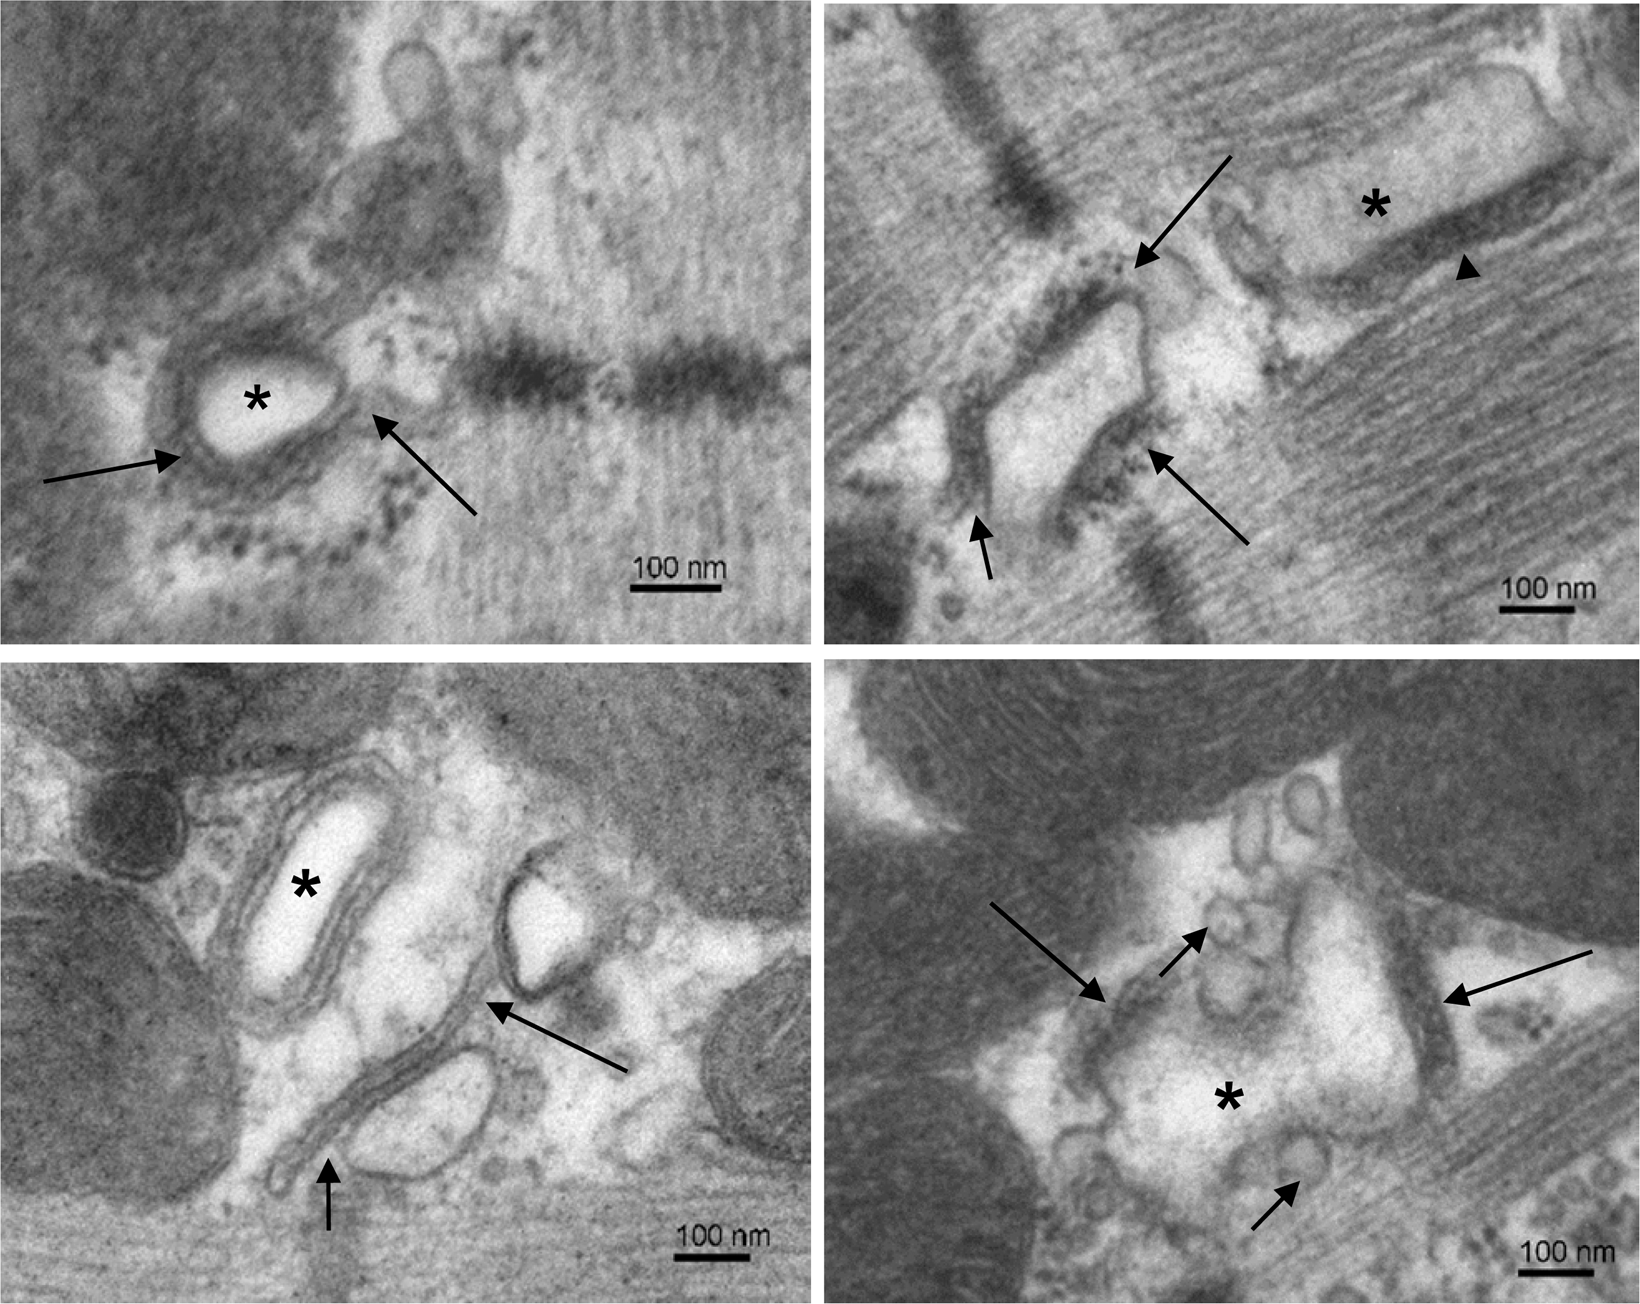

Figure 2

From: Structural variability of dyads relates to calcium release in rat ventricular myocytes

Examples of loose dyads. Electron micrographs selected to illustrate structural variability of the loose type of dyads. Top left: A dyad with a regular t-tubule (*) surrounded by a cisterna filled with homogenous electron-dense material and extending away from the t-tubule (arrows). Top right: Two dyads in a microdomain. The loose dyad between Z-lines has the junctional surface of cisterna partially deflected from the t-tubule (short arrow) and RyRs exposed to cytosol (long arrows). The compact dyad between A-bands of myofibrils contains a part of the longitudinal t-tubule (*) with well adherent cisterna (arrowhead). Bottom left: Two dyads in a microdomain. The dyad indicated by arrows is of the loose type because the junctional membrane of its cisterna deflects (short arrow) and extends (long arrow) from the t-tubule. The dyad made of regular t-tubule profile (*) is of the compact type of dyads. Bottom right: A dyad made of two cisternae (long arrows) and a deformed t-tubule (*). Numerous vesicles are present near the t-tubule (short arrows). Note: The left and the right columns show images taken from control and injured myocardia, respectively, but they represent characteristic dyads of both experimental groups.